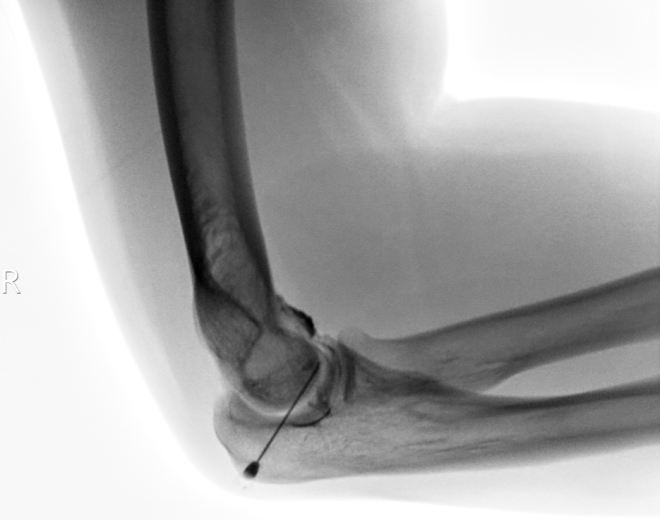

Metodika: Po punkci kloubu pod RTG kontrolou (obr.4) s podáním KL (Optiray 350) (MUDr. Šimánek Mir.) bylo podáno RF, následně aplikován 1 ml Depo-Medrol s 9 ml 1% Mesocainem.

/ Obr.4.: RTG snímek pravého lokte – punkce kloubu pod RTG kontrolou s podáním KL.